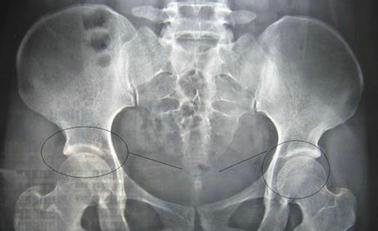

杜爱华主任在详细了解宋先生的情况之后,让他做了一个详细的检查,以确保治疗的正确性。检查结果显示:血沉89mm/h;C-反映蛋白34.25mg/L;HLA-B27(+);骶髂关节X片示:双侧骶髂关节面模糊、毛糙、不规则,关节附近骨质疏松,见斑点状及小囊状骨质破坏区及少许骨质增生硬化影,关节间隙模糊狭窄。根据这些检查结果,可以确诊为强直性脊柱炎。杜爱华主任根据检查数据为他制定了详细的治疗计划。

(图:患者来院时骶髂关节X线)